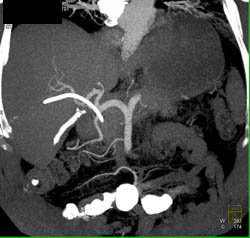

Metastases in A Fatty Liver